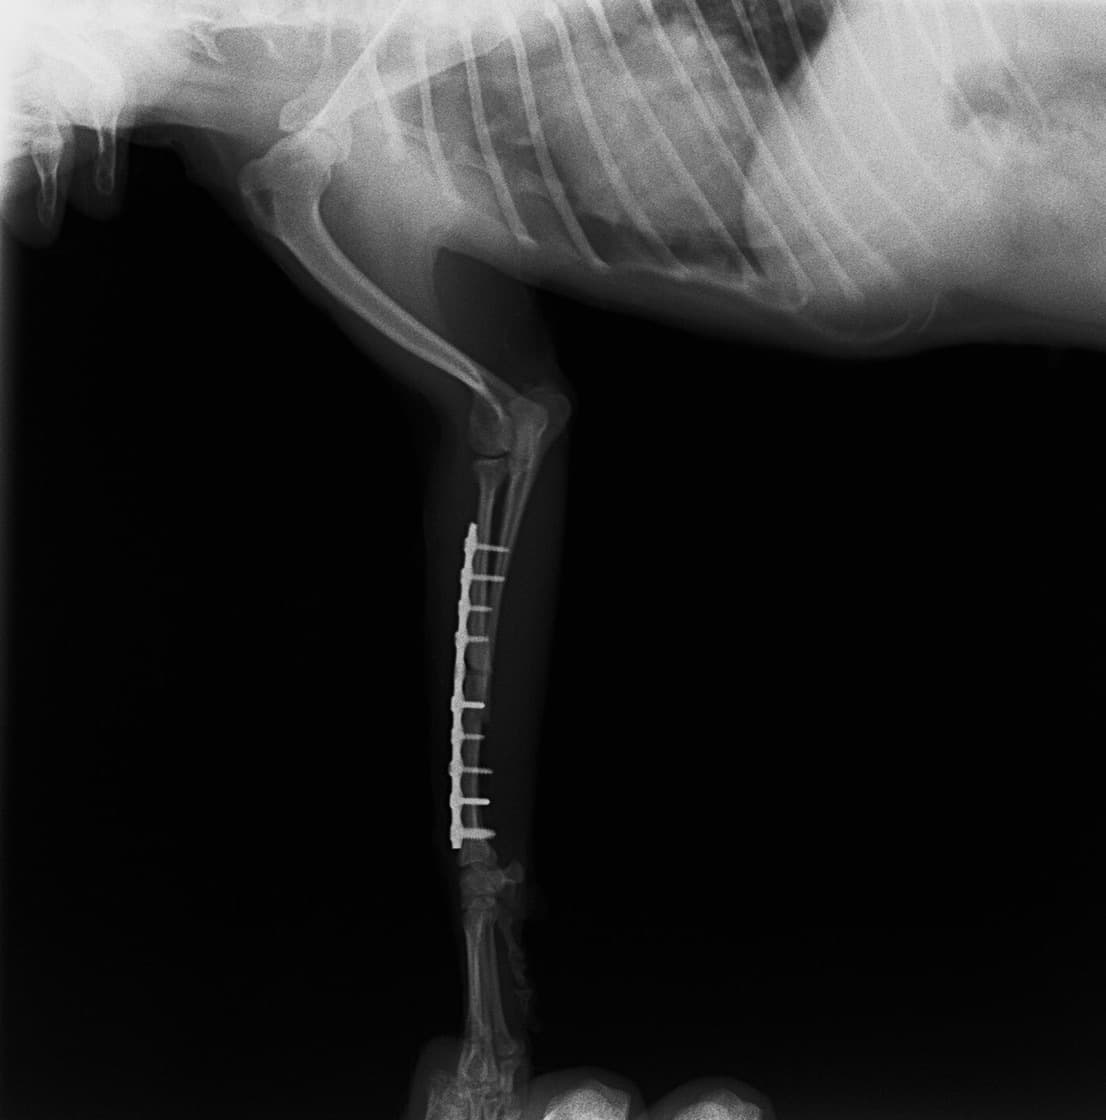

症例3:キルシュナーワイヤーのピンニングによる整復

ペルシャ猫 11ヶ月齢 雄

他院にて左大腿骨遠位の成長板骨折(salter-harrisⅠ型)が認められており、治療相談を目的として来院。当院にて、キルシュナーワイヤーを用いたピンニングにより骨折部位の整復を行いました。術後の経過は良好で、現在も経過観察中です。

術前レントゲン

術後レントゲン

Arthrex社のターゲティングデバイスを用いてピンニングの位置を調整することで、確実な固定を行っています。当院ではこの手術器具以外にも、人の手術にも使用される様々な器具を導入し、手術精度を高め、また医療メーカーと新しい器具の開発、試作にも取り組んでおります。